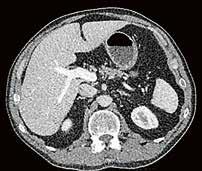

Fall 1:

Biphasische Abdomen-CT bei einer deutlich adipösen Patientin. Hier lässt sich sowohl Dosis sparen als auch die Qualität der Rekonstruktionen verbessern. Beispielsweise findet sich deutlich weniger Bildrauschen, insbesondere im Bereich der parenchymatösen

Portalvenöse Abdomen-CT. Auch hier ist die Dosis am Aquilion Prime SP mit AiCE geringer, zudem auch hier geringeres Bildrauschen mit sehr guter Abgrenzbarkeit, beispielsweise von Leberläsionen.

Abb. 1 a: biphasische Abdomen-CT, Canon Aquilion Prime, Rekonstruktion: AIDR 3D; DLP 1003,6 mGy × cm / 18,1 mSv. Abb. 2 a: biphasische Abdomen-CT, Canon Aquilion Prime, Rekonstruktion: AIDR 3D; DLP 1003,6 mGy × cm / 18,1 mSv. Abb. 1 b: biphasische Abdomen-CT, Canon Aquilion Prime, Rekonstruktion: AiCE; DLP 716,5 mGy × cm / 12,9 mSv. Abb. 2 b: biphasische Abdomen-CT, Canon Aquilion Prime, Rekonstruktion: AiCE; DLP 716,5 mGy × cm / 12,9 mSv. Oberbauchorgane.